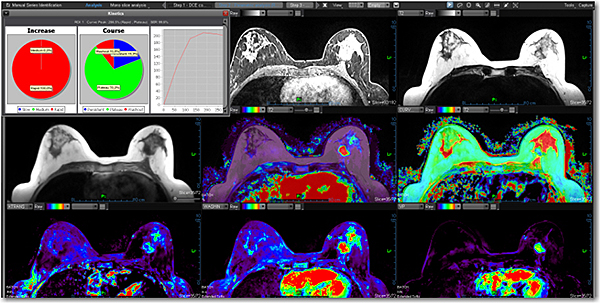

ПАКЕТИ ДЛЯ ЖІНОЧОГО ЗДОРОВ'Я